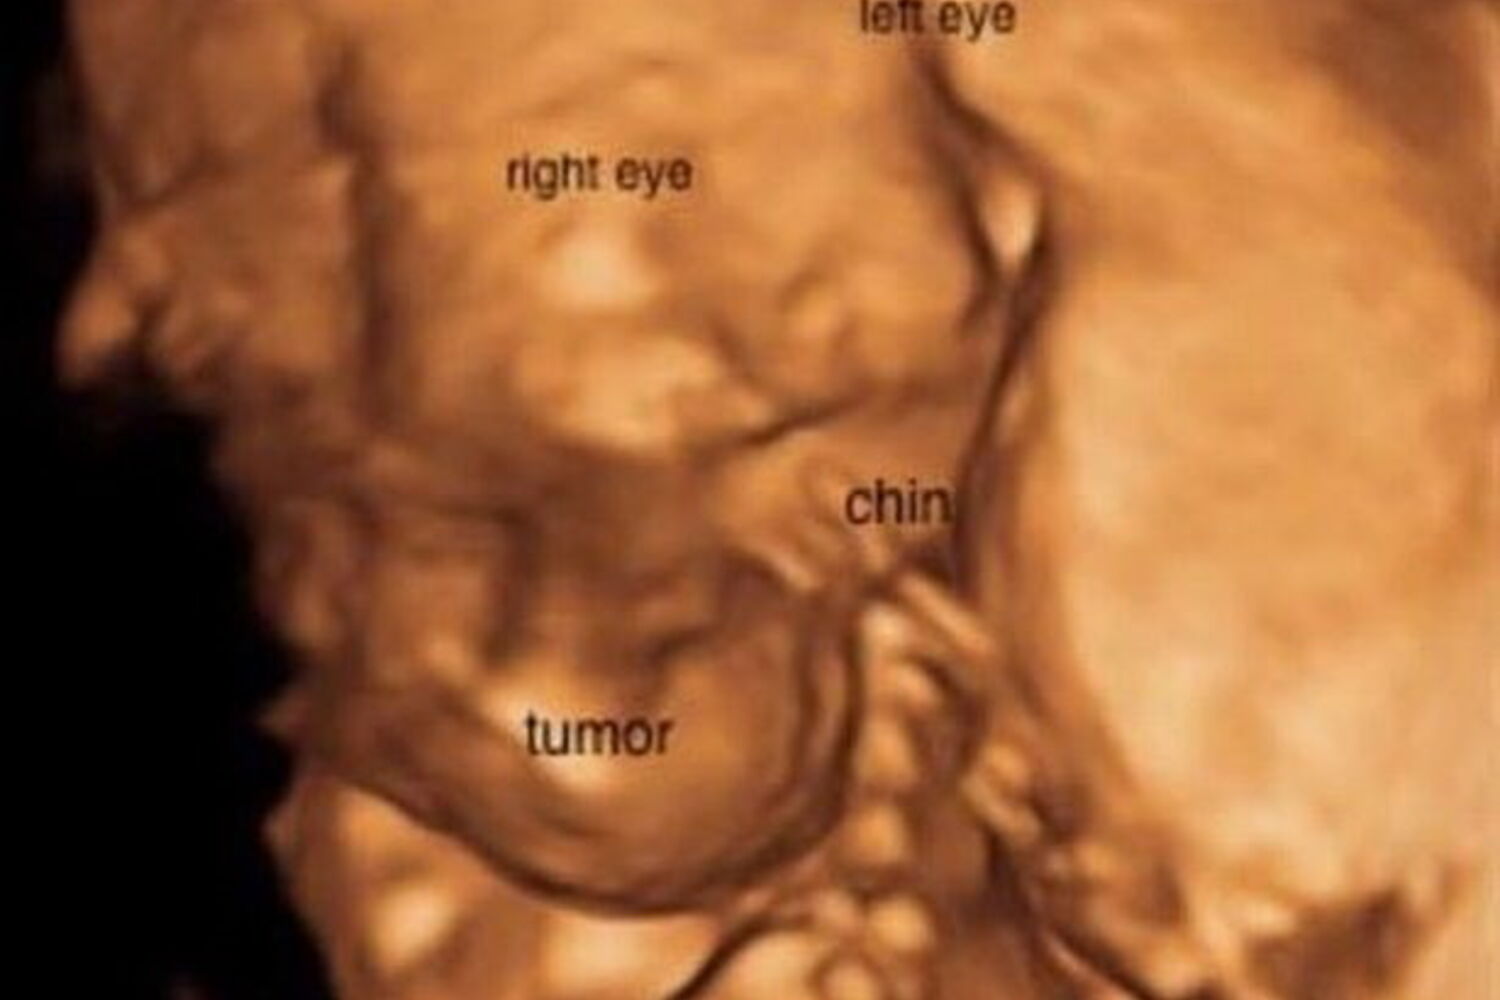

A jovem e o marido, Matt, ficaram radiantes quando descobriram que iam ser pais pela primeira vez. No entanto, algum tempo depois numa ecografia, foi detetado um tumor no pescoço da bebé, Omara, que abalou a esperança dos jovens.

Os médicos explicaram que o tumor poderia pôr em causa a saúde da mãe e da bebé, mas o casal resolveu esperar. O tumor parecia não se desenvolver mas, às 20 semanas de gestação, triplicou de tamanho e estava a ganhar metástases por todo o corpo da menina.

Destroçados, Lindsey e Matt foram informados que que havia apenas 1% de hipóteses e Omara sobreviver a toda a gravidez e que era muito provável que morresse assim que nascesse, uma vez que o tumor lhe estava a bloquear as vias respiratórias.